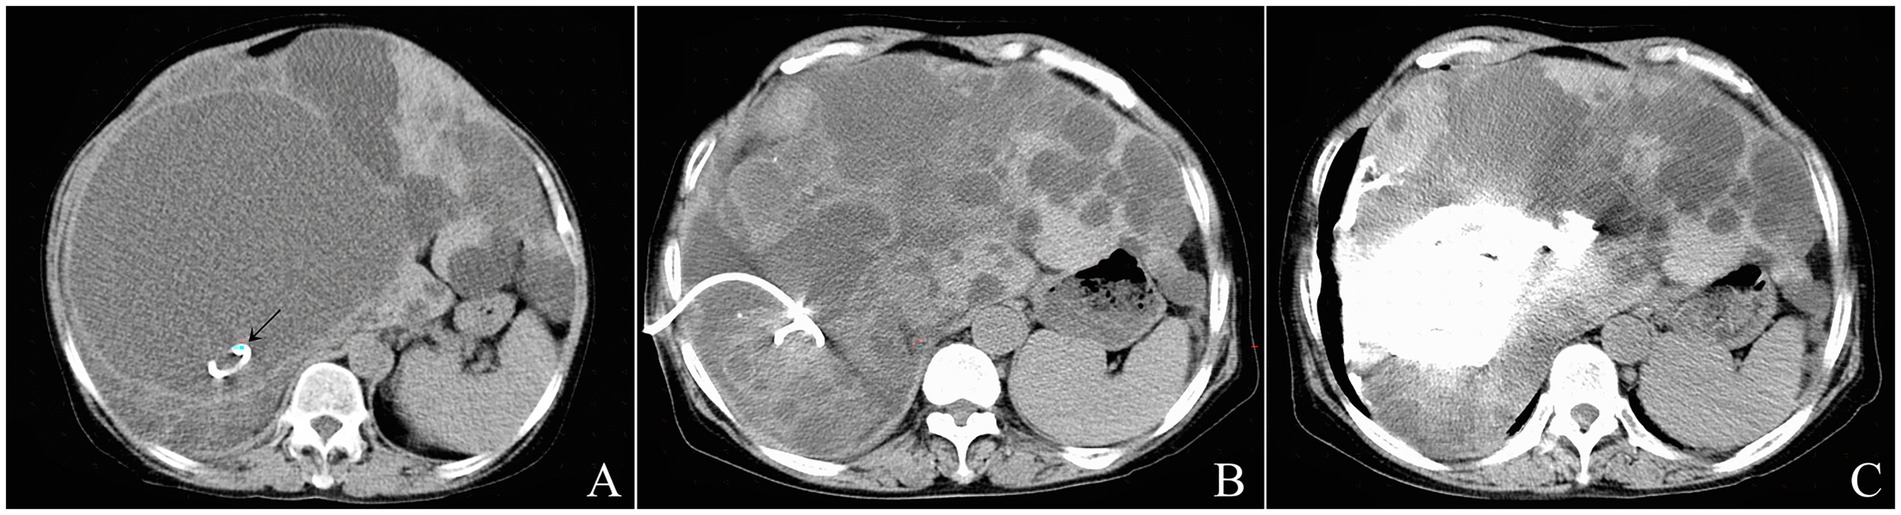

Large solitary cysts were punctured directly using a 21-gage Chiba Needle (Cook Medical LLC, Bloomington, United States) with a single-pass along the planned trajectory (Figure 1A). After confirming the correct needle position within the cyst cavity via a controlling CT scan, the needle core is removed, and 10 mL of the cyst content was aspirated for laboratory analysis. Next, 10 mL of undiluted iodinated contrast medium (Iohexol 300 mgI/mL, GE Healthcare, Shanghai, China) was injected into the cyst to ensure no communication between the cyst cavity and the biliary system, and no leakage into the peritoneal cavity (Figure 1B). The remaining cyst fluid with the contrast medium was then aspirated as completely as possible (Figure 1C). The total volume of the aspirated fluid was recorded. Subsequently, bleomycin hydrochloride (Takasaki Plant, Nippon Kayaku Co., Ltd., Tokyo, Japan) was dissolved in diluted contrast medium (1:1 mixture by volume of contrast medium and normal saline solution) at a total dose of 5 mg bleomycin per 100 mL cyst fluid, not to exceed 0.6–0.8 mg/kg body weight per patient. The amount of diluted contrast medium was equivalent to 5–10% of the aspirated fluid volume, not exceeding 10 mL. Bleomycin solution was injected into the aspirated cyst, and remained in the cyst cavity without extraction (Figure 1D). Finally, the needle was removed, and a postprocedure CT scan was performed to rule out leakage from the cyst and possible complications (Figure 1E).

CT scan images labeled A to E showing a liver cyst sclerotherapy procedure. Image A depicts needle insertion into the cyst. Images B to E show subsequent steps including contrast injection, fluid aspiration, bleomycin injection, and post-procedure assessment.

Figure 1. The single-pass single-needle puncturing technique of CT-guided percutaneous needle aspiration and bleomycin sclerotherapy for a 67-year-old male patient with solitary hepatic cyst. A 10-cm 21-gage Chiba needle was inserted into the cyst in the left liver lobe under CT guidance (A). After the first 10 mL of aspirated cyst fluid was sent to the laboratory for examination, 10 mL of diluted contrast media was injected into the cyst to confirm that there was no communication between the cyst and the biliary system (B). The cyst fluid was then evacuated almost completely (C). The repeat CT scan showed no leakage after injection of the half-dose Bleomycin solution contained diluted contrast media (D). The postprocedure CT scan showed that bleomycin solution was stayed in the cyst cavity (E).